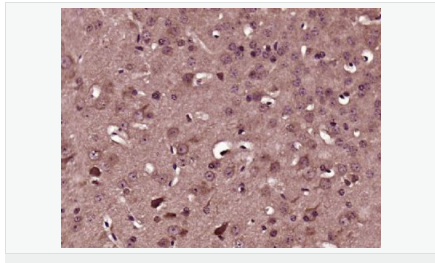

| 產(chǎn)品應(yīng)用 | WB=1:500-2000 ELISA=1:5000-10000 IHC-P=1:100-500 IHC-F=1:100-500 Flow-Cyt=0.2ug/Test IF=1:100-500 (石蠟切片需做抗原修復) not yet tested in other applications. optimal dilutions/concentrations should be determined by the end user. |

| 產(chǎn)品介紹 | ADAM23 is a non-catalytic metalloprotease-like protein. It is highly expressed in the brain, primarily in the amygdala, caudate nucleus, hypothalamus, thalamus, cerebral cortex and occipital pole, and weakly expressed in the heart. 3 isoforms are produced by alternative splicing, alpha, beta and gamma. ADAM23 may play a role in cell-cell and cell-matrix interactions. Subunit: Can bind to LGI1 and LGI4 (By similarity). Ligand for integrin alpha-V/beta-3. Subcellular Location: Cell membrane; Single-pass type I membrane protein. Isoform Gamma: Secreted. Tissue Specificity: Highly expressed in the brain and weakly expressed in the heart. In the brain, expressed prominently in the amygdala, caudate nucleus, hypothalamus, thalamus, cerebral cortex and occipital pole. Similarity: Contains 1 disintegrin domain. Contains 1 EGF-like domain. Contains 1 peptidase M12B domain. SWISS: O75077 Gene ID: 8745 Database links: Entrez Gene: 8745 Human Entrez Gene: 23792 Mouse Omim: 603710 Human SwissProt: O75077 Human SwissProt: Q9R1V7 Mouse Important Note: This product as supplied is intended for research use only, not for use in human, therapeutic or diagnostic applications. 細胞外基質(zhì)蛋白 |